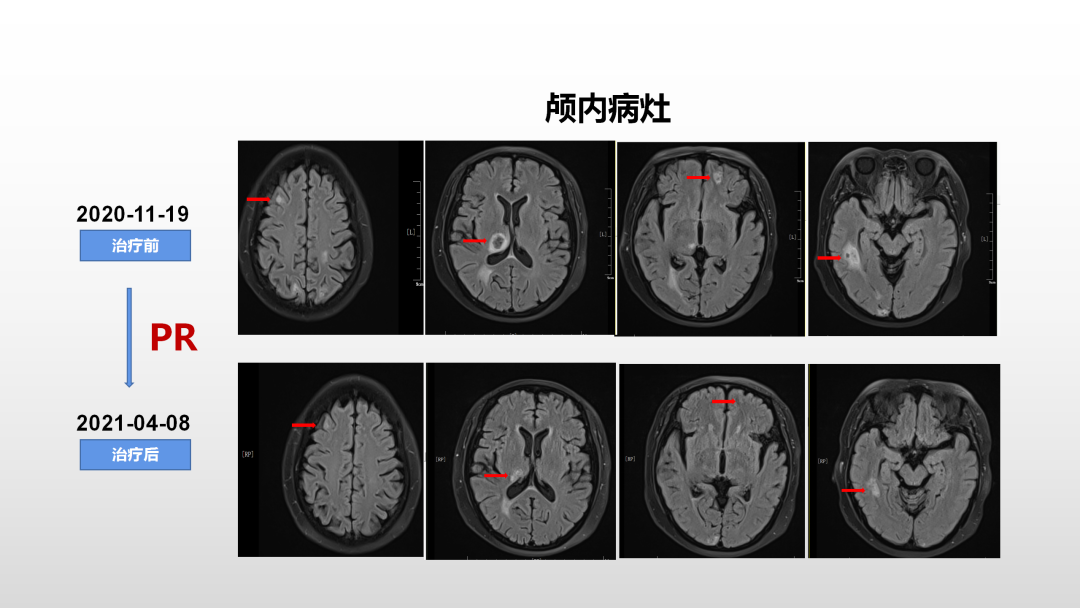

该患者系绝经后,HER2+亚型,肝、肺、胸膜、骨多发转移,一线妥妥双靶治疗期间出现脑转移,颅外病灶稳定,目前突出问题是脑转移。CSCO AI提示患者骨转移风险,同时存在曲妥珠单抗、帕妥珠单抗耐药,推荐解救化疗联合靶向治疗,并在此基础上使用骨改良药物。基于PHENIX研究中脑转移患者使用吡咯替尼联合卡培他滨较单用卡培他滨延长3个月mPFS,故1级推荐本方案,联合唑来膦酸治疗。经脑部放疗及上述方案系统治疗后,患者颅内病灶部分缓解,头晕、头痛、呕吐明显缓解,目前精神、体力状况良好,仍处于该方案治疗中。